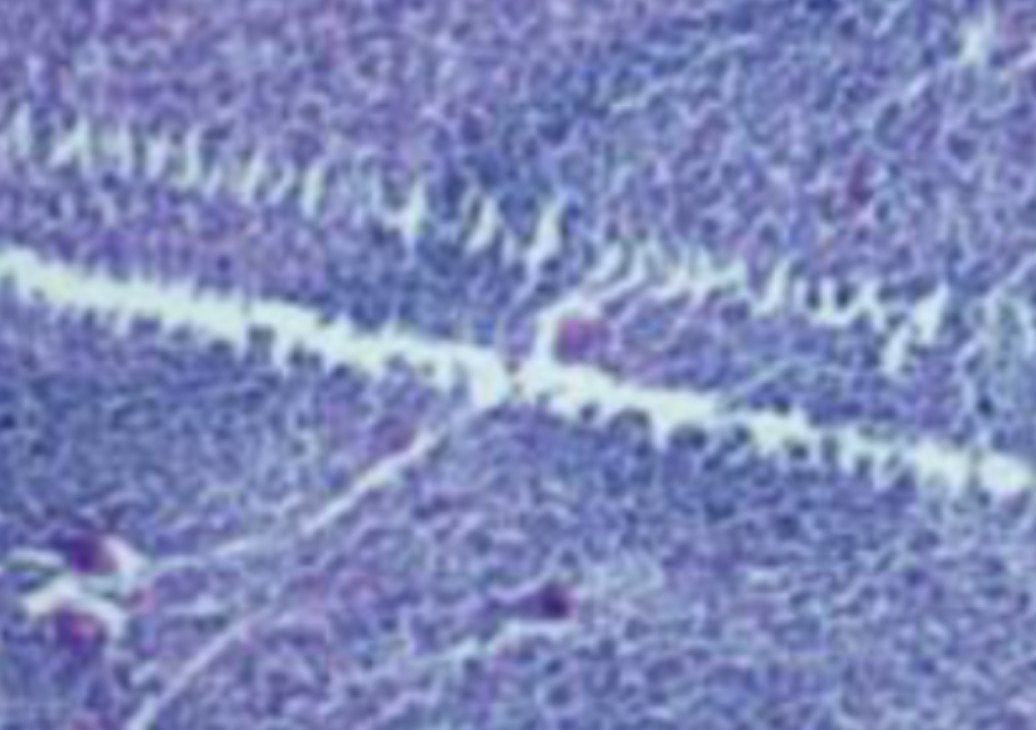

形成原因:切片经梯度乙醇处理后没有完全脱水,导致二甲苯透明、中性树胶封固后残留大量水分。 解决方法:首先移去盖玻片,用二甲苯溶解封固剂如中性树胶,再将切片置入无水乙醇内,待切片重新脱水完全后,用二甲苯透明处理,中性树胶封固。要注意所有用于脱水和透明的液体,在使用一定时间后,应及时更换。 二、细胞核呈红、棕色 形成原因:苏木精染色液过度氧化,切片在苏木精染液染色后返蓝不足。 解决方法:每次染色之前检查苏木精染色液的染色能力,发现苏木精染色液氧化过度应及时更换。此外,切片经苏木精染色后,要给切片以足够的蓝化时间,蓝化过程可用流水、温水、弱碱性溶液(如稀氨水或0.2%碳酸氢钠)等处理。 三、切片在脱蜡后出现大片白色斑点 形成原因:由于烤(烘)片温度太低,切片上的组织蜡膜在脱蜡前没有充分烤(烘)融化。或是因为切片在二甲苯液中停留时间不足,或二甲苯使用过久,造成的脱蜡不彻底。 解决方法:若是由于切片烤(烘)温度低所致,可以先用二甲苯去除切片上的封固胶,然后重新用二甲苯脱去切片上的石蜡,再进行后续染色。若是由于切片在脱蜡的二甲苯中停留时间不足或脱蜡二甲苯使用过久浓度不足所致,则需将切片退回到二甲苯中,停留较长时间,或更换二甲苯液体重新脱蜡,再入乙醇重新脱二甲苯,入0.5%盐酸水溶液褪色后,重新HE染色。 四、细胞核苍白暗淡,即苏木精染色太淡 形成原因:切片在苏木精染色液停留时间太短;苏木精染色液过度氧化,失去染色能力,不能再继续使用;分化步骤处理时间过长;固定不及时。此外值得注意的是,若骨组织细胞核暗淡,大多是脱钙过度造成的。 解决方法:切片重新染色。如果组织在酸性固定液(如Zenker、Bouin)或非中性缓冲甲醛液固定时间过长,细胞核染色能力将减弱,需增加其在苏木精染色液的时间,或用一些方法增加组织的嗜碱性,以改善细胞核的着色。例如,上述组织玻片可以使用Weigert铁苏木精染色液。如果组织是用Zenker液固定的,可将切片脱蜡后放在5%碳酸氢钠溶液3~4h,流水冲洗5min后染色。如果组织是用Bouin液固定的,可将切片脱蜡后放在5%碳酸锂1h,流水冲洗10min后染色。 五、细胞核过染,苏木精染液占据了细胞质 形成原因:玻片在苏木精染色液停留时间过长,或是切片太厚、分化步骤时间太短。 解决方法:如果不是因为切片太厚(用显微镜仔细上下微调,只有一二层细胞核层次),就需将切片进行脱色、漂白、重新染色,适当调整染色和分化时间。但如果确定是由于切片太厚导致的细胞核过染,则需要重新切片。 六、伊红着色淡 形成原因:可能是伊红染液pH值大于5,也可能是蓝化液残留过多,切片太薄,或是切片经伊红染色后在乙醇脱水时间过长。 解决方法:检查伊红染液pH值,必要的话,用乙酸将其调节在4.6~5.0之间,从而使伊红染色色彩艳丽。此外,确保每次蓝化步骤完成后,使用的弱碱性溶液被充分洗去,玻片上没有残留的弱碱性溶液。最后,检查切片的厚度,且脱水时不要让切片在低浓度乙醇中停留时间过长,因为含水多的低浓度乙醇会将切片伊红的颜色分化掉。 七、细胞质过染、分色不足 形成原因:伊红染色液浓度太高,特别是存在焰红燃料、四溴四氯荧光素钠。切片在伊红染色时间过长,或是切片在伊红染色后经乙醇脱水步骤时时间太短,而使乙醇分化伊红的作用不能产生,都能够使细胞质过染。 解决方法:适当稀释伊红染色液,减少伊红染色时间,或使切片在乙醇脱水等步骤时,停留时间相对均匀。同样,也要检查切片的厚度是否合适。 八、切片中出现蓝黑色沉淀物 形成原因:苏木精染色液中的金属膜黏附在玻片上。 解决方法:染色前仔细过滤苏木精染色液,建议使用半氧化苏木精染色液,如Gill苏木精染色液,可以避免过多的金属膜产生。 九、光镜下切片某些区域难以聚焦 形成原因:盖玻片上可能有封固切片的封固剂。 解决方法:移去盖玻片,重新用干净的盖玻片封片。检查切片封片方法,是人工手工封法,还是机器自动封法,如有问题及时调整。 十、封固剂从盖玻片与载玻片之间的缝隙回缩 形成原因:盖玻片弯曲或不平整,或是封固剂含二甲苯过多,稀释过度。 解决方法:移去盖玻片,重新找一张盖玻片,用干净的封固剂封片。如用手工封片法,保证在封固结束时,封固剂容器盖子为紧闭状态。且尽量使用小的容器盛装封固剂,一旦封固剂太黏稠,就可以选择废弃。 十一、细胞核呈灰蓝状态 形成原因:可能由于组织处理温度过高、过热,在液体石蜡中停留的时间过长。或是固定时间太短后,直接在高浓度的乙醇中进行了脱水处理。 解决方法:理论上来说,仅在组织浸蜡步骤才进行加热,组织不能在热蜡液中停留太久。如果由于某些原因不能进行下一步包埋处理,可将组织连同塑料包埋盒一并放置在室温空气中,冷却凝固,以备包埋。待需要包埋时再重新加温直至石蜡融化即可。组织在处理前必须确保固定良好,脱水最好能从低浓度的乙醇开始。 十二、类色素的点状结晶和黑色光滑细胞核 形成原因:这种裸核改变是因为切片封片前放置在空气中的时间太长,以至于二甲苯挥发,切片干燥。 解决方法:移去组织切片上的盖玻片和封固剂,重新处理。将切片水洗数分钟,然后重新脱水、透明、封固。封片过程中要保持组织切片的轻度湿润,尽量不要让其干燥。 十三、染色过淡或过浓 解决方法:如果染色过淡,可以增加染色剂的浓度、延长染色时间或更换新鲜的染色剂;如果染色过浓,则应减少染色剂的浓度或缩短染色时间。 十四、切片出现叠加褶皱 形成原因:新购买的玻片洁净度不够、用镊子撑开切片时操作不够熟练未能平整伸展,或玻片表面有油脂,切片粘贴不牢。另外,烤片时间不足、烤片温度过低或切片过厚造成切片脱落,都会造成重叠或有皱褶的情况。 解决方法:新购买的玻片最好能用硫酸清洁液浸泡一晚,然后流水冲洗干净。在适宜的温度下烤片时间宁长勿短,保证有充足的烤片时间和温度。另外,切片刀要锋利,才能切出厚薄适宜的切片,保证切片不会因为过厚而脱落。 十五、组织残缺不全或有刮划痕迹 形成原因:组织残缺不全是由于切片时修整蜡块时深度不够、组织没有全部暴露于切面。切片的刮划痕迹是由于切片刀的刀锋有缺口、包埋的组织有异物,或是钙化组织、骨组织及包埋石蜡有沙粒造成的。 解决方法:修整蜡块时保证组织块全部暴露于切面,切片时保证切片刀的锋利没刀口。同时在组织取材时去除手术异物和钙化组织。最后,骨组织要完全脱钙,这样可以保证切片的完整和平整美观。 *注:由于实验中导致结果出现误差的原因多种多样,以上内容仅供参考,具体根据实际情况进行判断。